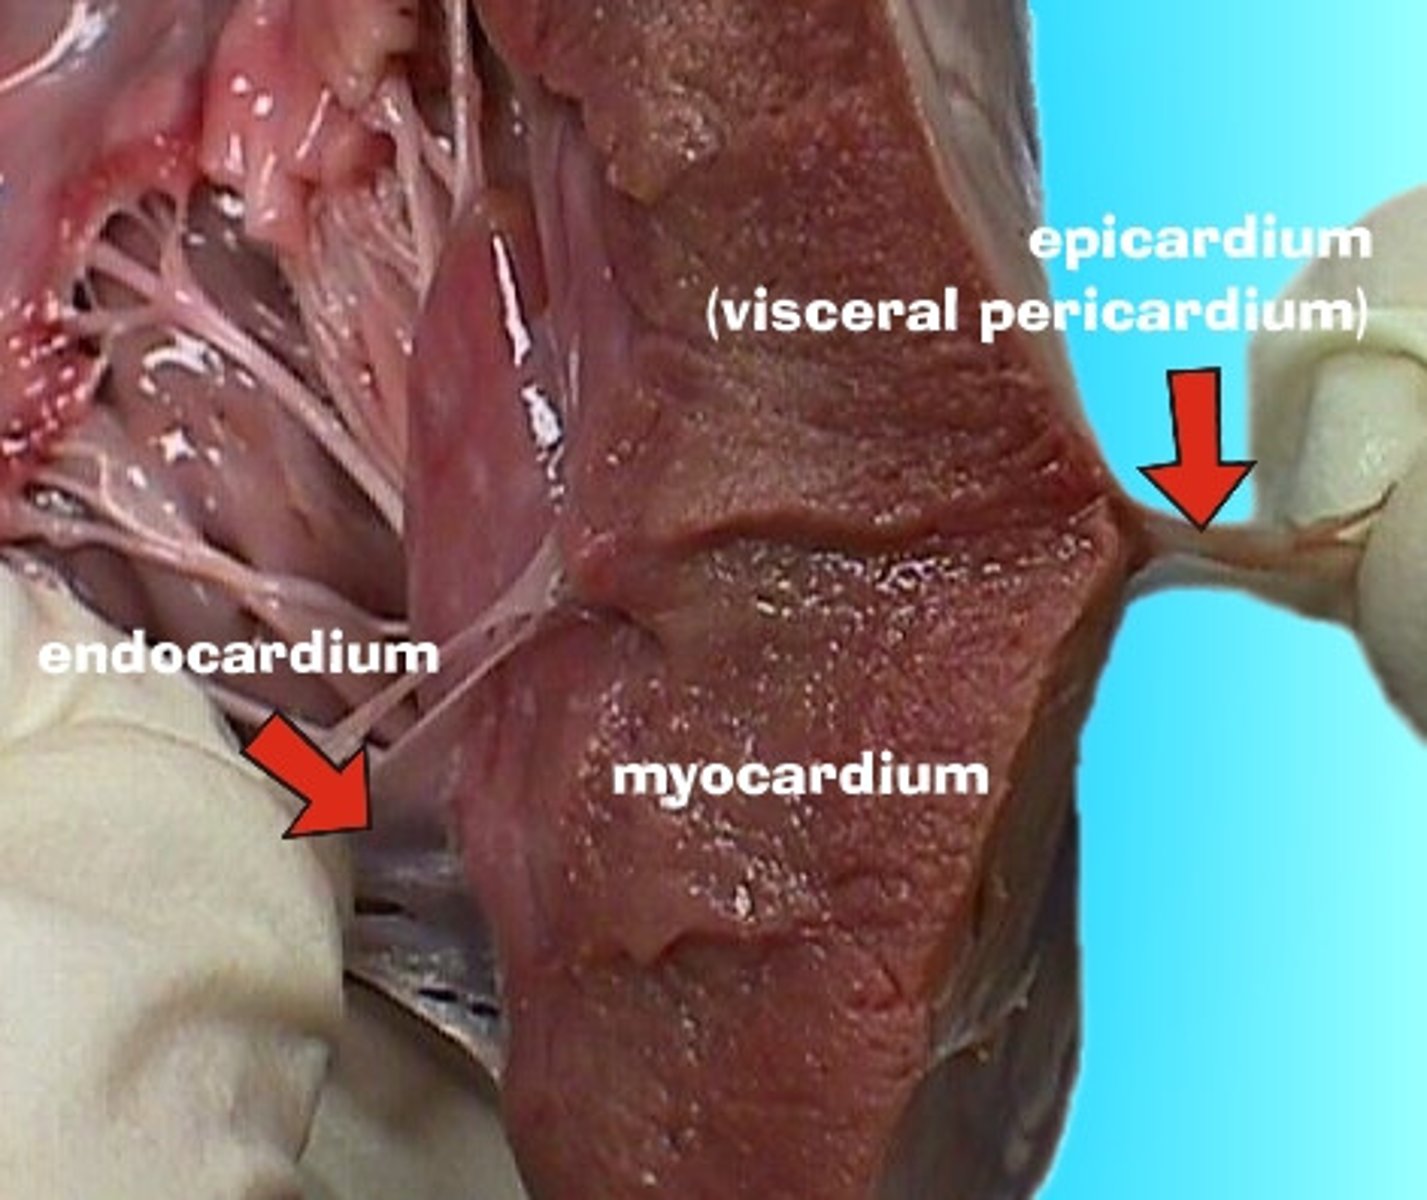

osierdzie

pericardium

Jakie rodzaje osierdzia wyróżniamy?

surowicze i włókniste

osierdzie surowicze

serous pericardium

Z jakich części składa się osierdzie surowicze?

z blaszki trzewnej i ściennej

blaszka trzewna osierdzia surowiczego

visceral layer of serous pericardium

blaszka trzewna osierdzia surowiczego inaczej

nasierdzie

nasierdzie

epicardium

blaszka ścienna osierdzia surowiczego

parietal layer of serous pericardium

Gdzie znajduje się jama osierdzia?

między blaszką ścienną i trzewną osierdzia surowiczego

jama osierdzia

pericardial cavity

Jak jest położone nasierdzie?

ściśle zrośnięte z powierzchnią zewnętrzną serca

Jak odróżnić blaszkę ścienną osierdzia surowiczego i osierdzie włókniste?

Nie da się - są ze sobą zrośnięte

Co znajduje się w jamie osierdzia?

płyn surowiczy umożliwiający ślizganie się blaszek osierdzia